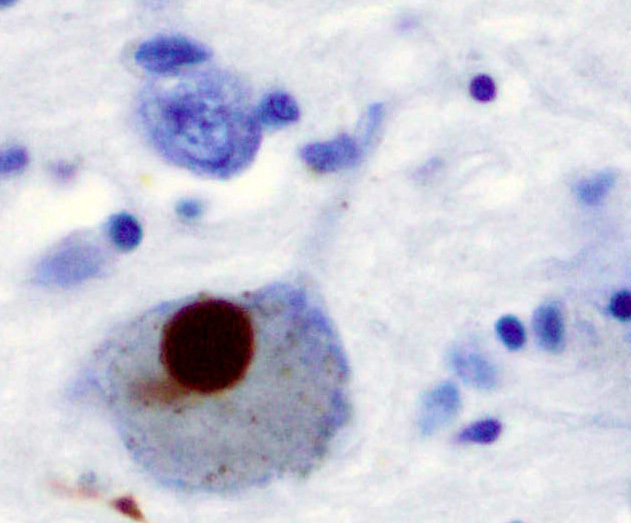

Нейродегенеративные заболевания, такие как болезнь Паркинсона, Альцгеймера и прионные инфекции, во многом связаны с накоплением в мозге неправильно свернутых белков, образующих токсичные амилоидные агрегаты. Особый интерес для науки представляет взаимодействие между разными классами таких белков, например, прионного белка (PrP) и альфа-синуклеина (α-syn), ключевого игрока в развитии болезни Паркинсона. Однако данных о таких взаимодействиях накоплено недостаточно, и они зачастую противоречивы.

В ходе работы исследователи выделили и изучили свойства N-концевого (аминокислоты 23–124) и C-концевого (аминокислоты 103–234) фрагментов овечьего прионного белка. Оказалось, что изолированный C-концевой фрагмент, хотя и содержит больше бета-структур (то есть ближе к патологической конформации), чем полноразмерный белок, но обладает пониженной способностью к образованию амилоидных фибрилл. В то же время, N-концевой фрагмент не только сам не формирует фибриллярных структур, но и подавляет амилоидную трансформацию полноразмерного прионного белка.

Еще более интригующим оказалось влияние прионного белка на альфа-синуклеин. Ученые обнаружили, что полноразмерный PrP, его N-концевой фрагмент и даже зрелые фибриллы PrP резко ускоряют агрегацию как нормального альфа-синуклеина, так и его мутантной формы A53T, связанной с ранним развитием паркинсонизма. Однако ускорение не приводило к образованию типичных длинных структурированных фибрилл. Вместо этого формировались отдельные разнородные агрегаты.